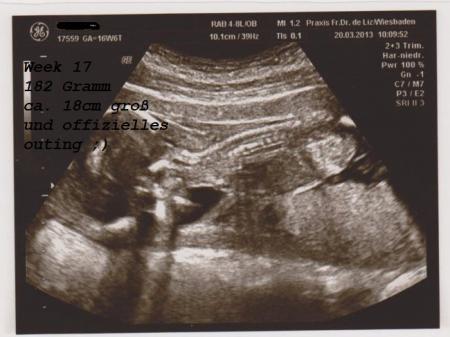

Heeeey ;) gestern war ich zum kontrolltermin wieder beim frauenarzt... Sie hat erst vaginal geschaut aber man sah nur den kopf ;) Dann auf der bauchdecke.. und sie da ... EIN JUNGE ;) Sie sagte 100% sie ist sich sehr sicher und hat mir für den papa das beste stück auch fotografiert ;) Der kleine Mann ist jetzt ca., 18 cm groß.. und wiegt ungefär 182 gramm (sind ja schätzwerte anhand von versch. ausmessungen ) bin happy... anbei 2 bilder die ich gestern erhalten habe ;) Aber irgendwie trau ich mich noch nicht zu shoppen lol... es gab ja auch viele fehldiagnosen ;) wie war das bei euch? Wenn die ärztin sagte SICHER ... oder habt ihr vllt. so ein ähnliches foto wie meins und es war doch ein mädel? Lg Sina

Bild zu Juhuu hab ein Outing ;) - Schwanger - wer noch? Rund um die Schwangerschaft